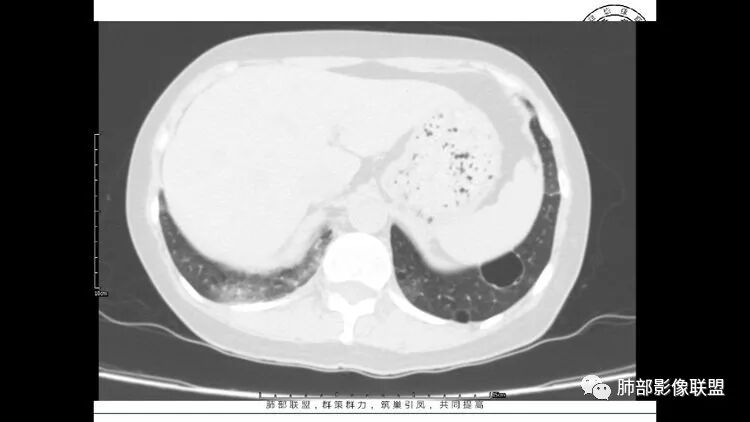

胸CT:1.双肺多发囊性变,以中下肺为主,病变边缘可见肺动脉,部分囊内可见分隔及肺动脉,双下部分肺野周围可见小叶中心结节及树丫征。

2 左肺上叶尖后段 右肺上叶前段 右肺下叶外基底段 结节影,边界清楚,可见柔软毛刺,左肺下叶后基底段混合密度影。

患者中年女性,因右眼红痛1天就诊。胸CT:双肺多发囊性变及结节影,囊以中下肺为多,部分囊内可见分隔及肺动脉,结节部分为实性,部分为混合性,边缘光滑,未见明显毛刺、棘突、胸膜牵拉及血管集束征象。双中下可见支气管扩张及树丫征。淋巴结无明显肿大。综合考虑:一元淋巴细胞间质性肺炎。多元鉴别肺腺癌并转移等恶性病变。

中年女性,因“角膜炎”入院,自用眼液2年,(眼干?)肺部:双肺多发类圆形薄壁气囊+实性结节+GGO,下肺分布为主,纵隔淋巴结肿大,考虑淋巴系统增殖,LIP可能性大,可能继发于干燥综合症;左肺下叶的混合磨玻璃结节形迹可疑,边界清晰,内部疑似空泡,扩张扭曲支气管,极像肺癌,伴双肺转移?待排吧

左肺下叶混杂密度病灶,其内可见空泡,周围ggo清楚,考虑浸润性腺癌。双肺散在多发薄壁囊腔和实性结节,以胸膜下及血管旁分布位于,气囊可见血管贴边征,双肺小叶间隔及中央间质增厚,局部可见磨玻璃影及树芽征,纵隔内淋巴结肿大,考虑LIP

综上,考虑左下肺浸润性腺癌+LIP

双肺多发大小不等囊腔,可见薄壁,部分囊腔内可见血管影,伴双肺多发结节,结合患者眼病及类风湿病史,考虑LIP可能大。另左肺下叶磨玻璃结节,边界清晰,内可见空泡,伴纵膈多发肿大淋巴结,不除外浸润性腺癌可能。

常规分析:右眼红疼1天,滴眼史两年,有类风湿病史,考虑有干燥综合征(SS)可能,需要了解自免抗体检测情况,双肺囊变需要考虑LIP,另右上叶前段GGO要鉴别腺癌或转移可能,右下叶背段多发树芽改变,双肺多发实性小结节,结核?左下肺混合性GGO考虑侵润性腺癌可能,双侧胸膜下多发结节,部分合并GGO改变,右侧腋窝及纵隔淋巴结多见,转移?最后问题来了,这个病人一元(腺癌合并转移,包括整个囊变,实性结节,胸膜下都是转移)?二元(LIP合并腺癌伴转移或者淀粉样变基础上的LIP)?三元(LIP+结核+腺癌伴转移)?

LIP影像重要线索一句话:

双肺下叶分布为主的间质改变(磨玻璃影、小叶间隔增厚)、散在气囊影(常有血管贴边)、边界不清小结节